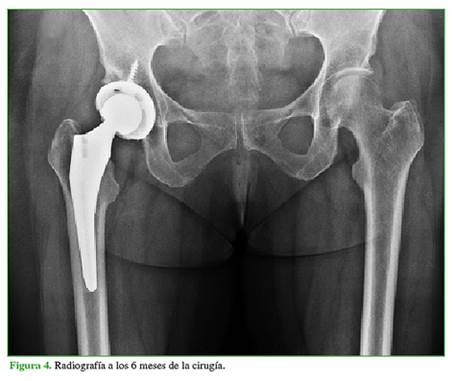

Sobre la base de estos hallazgos, se diagnosticó una fractura por insuficiencia subcondral del acetábulo derecho. En primera instancia y luego de haberle explicado el pronóstico probable, se decidió realizar una infiltración bajo tomografía computarizada con ácido hialurónico y un corticoide de depósito, y se le indicó continuar con descarga de la extremidad afectada mediante un bastón, durante seis semanas. El dolor mejoró levemente luego de tres meses, pero aún continuaba con importantes limitaciones para deambular más de 100 metros. Finalmente, luego de cuatro meses desde la consulta inicial en nuestro centro y ante la progresión de los síntomas, se sometió a una artroplastia total de cadera derecha no cementada (Figura 3). Los controles radiográficos a los tres y seis meses de la cirugía mostraron implantes estables y la paciente había reanudado su actividad habitual sin restricciones (Figura 4).